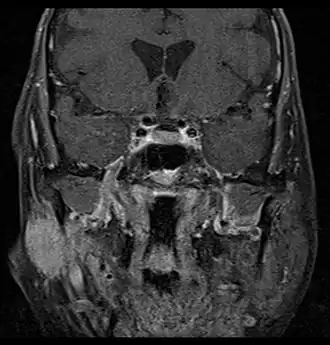

Coronale MRI die cystisch carcinoom van de rechter oorspeekselklier toont met perineurale uitzaaiing van de tumor: de tumor vindt zijn oorsprong in de rechter oorspeekselklier en verspreidt zich langs de nervus trigeminus via de nervus auriculotemporalis die zich intracraniaal uitstrekt door het foramen ovale bij de schedelbasis richting de holte van Meckel. -

Coronale MRI die cystisch carcinoom van de rechter oorspeekselklier toont met perineurale verspreiding van de tumor langs de aangezichtszenuw die zich uitstrekt tot het foramen stylomastoïde -